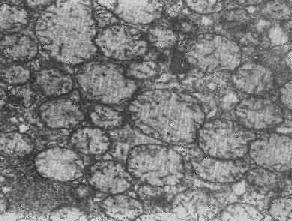

四、线粒体线粒体(mitochondrion)是细胞内主要的能量形成所在,故不论在生理上或病理上都具有十分重要的意义。 线粒体为线状、长杆状、卵圆形或圆形小体,外被双层界膜。外界膜平滑,内界膜则折成长短不等的嵴并附有基粒。内外界膜之间为线粒体的外室,与嵴内隙相连,内界膜内侧为内室(基质室)(图1-8)。在合成甾类激素的内分泌细胞(如肾上腺皮质细胞、卵甾滤泡细胞、睾丸的Leydig细胞等),线粒体嵴呈小管状。内外界膜的通透性不同,外界膜的通透性高,可容许多种物质通过,而内界膜则构成明显的通透屏障,使一些物质如蔗糖和NADH全然不能通过,而其他物质如Na+ 和Ca 2+等也只有借助于主动运输才能通过。线粒体的基质含有电子致密的无结构颗粒(基质颗粒),与二价阳离子如Ca2+及Mg2+具有高度亲和力。基质中进行着β氧化、氧化脱羧、枸橼酸循环以及尿素循环等过程。在线粒体的外界膜内含有单胺氧化酶以及糖和脂质代谢的各种转移酶;在内界膜上则为呼吸链和氧化磷酸化的酶类。 线粒体是对各种损伤最为敏感的细胞器之一。在细胞损伤时最常见的病理改变可概括为线粒体数量、大小和结构的改变: 1.数量的改变 线粒体的平均寿命约为10天。衰亡的线粒体可通过保留的线粒体直接分裂为二予以补充。在病理状态下,线粒体的增生实际上是对慢性非特异性细胞损伤的适应性反应或细胞功能升高的表现。例如心瓣膜病时的心肌线粒体、周围血液循环障碍伴间歇性跛行时的骨骼肌线粒体的呈增生现象。 线粒体数量减少则见于急性细胞损伤时线粒体崩解或自溶的情况下,持续约15分钟。慢性损伤时由于线粒体逐渐增生,故一般不见线粒体减少(甚至反而增多)。此外,线粒体的减少也是细胞未成熟和(或)去分化的表现。 2.大小改变 细胞损伤时最常见的改变为线粒体肿大。根据线粒体的受累部位可分为基质型肿胀和嵴型肿胀二种类型,而以前者为常见。基质型肿胀时线粒体变大变圆,基质变浅、嵴变短变少甚至消失(图1-9)。在极度肿胀时,线粒体可转化为小空泡状结构(图1-10,图1-11)。此型肿胀为细胞水肿的部分改变。光学显微镜下所谓的浊肿细胞中所见的细颗粒即肿大的线粒体。嵴型肿较少见,此时的肿胀局限于嵴内隙,使扁平的嵴变成烧瓶状乃至空泡状,而基质则更显得致密。嵴型肿胀一般为可复性,但当膜的损伤加重时,可经过混合型而过渡为基质型。 线粒体为对损伤极为敏感的细胞器,其肿胀可由多种损伤因子引起,其中最常见的为缺氧;此外,微生物毒素、各种毒物、射线以及渗透压改变等亦可引起。但轻度肿大有时可能为其功能升高的表现,较明显的肿胀则恒为细胞受损的表现。但只要损伤不过重、损伤因子的作用不过长,肿胀仍可恢复。 线粒体的增大有时是器官功能负荷增加引起的适应性肥大,此时线粒体的数量也常增多,例如见于器官肥大时。反之,器官萎缩时,线粒体则缩小、变少。

图1-10肾小管上皮细胞线粒体部分空泡变

图1-11 线粒体肿胀(基质型)空泡变(心肌缺氧) 3.结构的改变 线粒体嵴是能量代谢的明显指征,但嵴的增多未必均伴有呼吸链酶的增加。嵴的膜和酶平行增多反映细胞的功能负荷加重,为一种适应状态的表现;反之,如嵴的膜和酶的增多不相平行,则是胞浆适应功能障碍的表现,此时细胞功能并不升高。 在急性细胞损伤时(大多为中毒或缺氧),线粒体的嵴被破坏;慢性亚致死性细胞损伤或营养缺乏时,线粒体的蛋白合成受障,以致线粒体几乎不再能形成新的嵴。 根据细胞损伤的种类和性质,可在线粒体基质或嵴内形成病理性包含物。这些包含物有的呈晶形或副晶形(可能由蛋白构成),如在线粒体性肌病或进行性肌营养不良时所见(图1-12);有的呈无定形的电子致